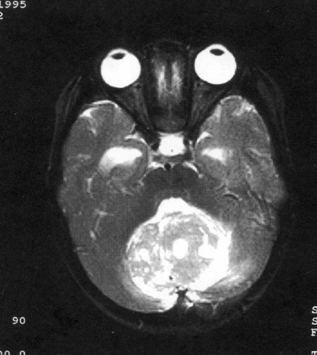

问题 病历摘要:??患儿男性,11岁。半年前开始出现行走不稳,常无故跌倒。半月前出现发作性剧烈头痛,伴恶心呕吐。体检:T36℃,P100次/分,R22次/分,BP100/60mmHg,神清,言语较缓慢,双眼外展约不及边,双眼侧视时有小幅度水平眼震。四肢肌力正常,右上肢肌张力较低,坐位姿势不稳,常不自主摇晃,双上肢指鼻不准,行走蹒跚步态,足距扩大,身前倾。 患儿目前出现了哪些方面的临床症状